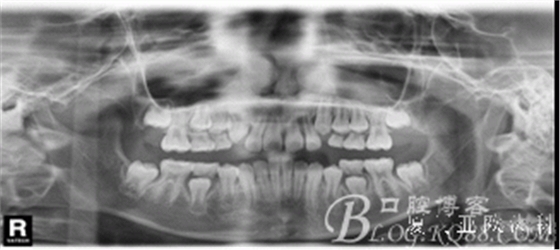

全頜曲面斷層片:尚未萌出的恒牙牙胚均存在。

診 斷:安氏I類錯合(III類傾向)。骨骼III類關系。凹面型:上頜劣生長、下頜過生長。上頜尖牙萌出間隙不足。前牙骨性反咬合。